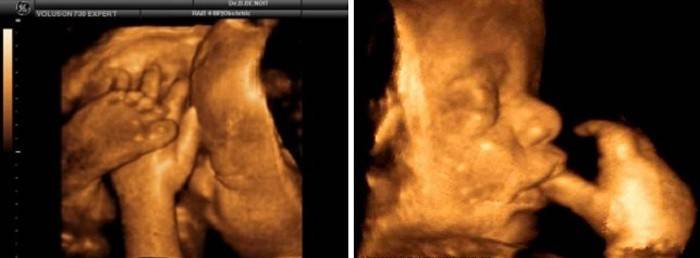

A 41ª semana é o final do calendário nono mês, e no décimo mês obstétrico, a gravidez está totalmente terminada, você já cruzou a linha de 40 semanas. Mas às vezes há tendências para mover a gravidez ou datas calculadas incorretamente e, portanto, você ainda pode estar grávida. Na realidade, a duração da gravidez pode depender de numerosos fatores - da duração dos ciclos menstruais, do tempo que o óvulo sai (ovulação) e da hereditariedade, da idade e do estado hormonal da gestante. Portanto, é provável que você possa dar à luz às 41 semanas de gestação, não é perigoso. Ao mesmo tempo, o bebê já está totalmente pronto para enfrentar este mundo, todos os processos necessários de desenvolvimento intra-uterino são completados, todos os sistemas e órgãos estão trabalhando ativamente, e tornou-se extremamente lotado dentro do útero devido ao crescimento contínuo do feto e ganho de peso. Em média, ele agora pesa cerca de 3.700 ge sua altura chega a 54 cm.